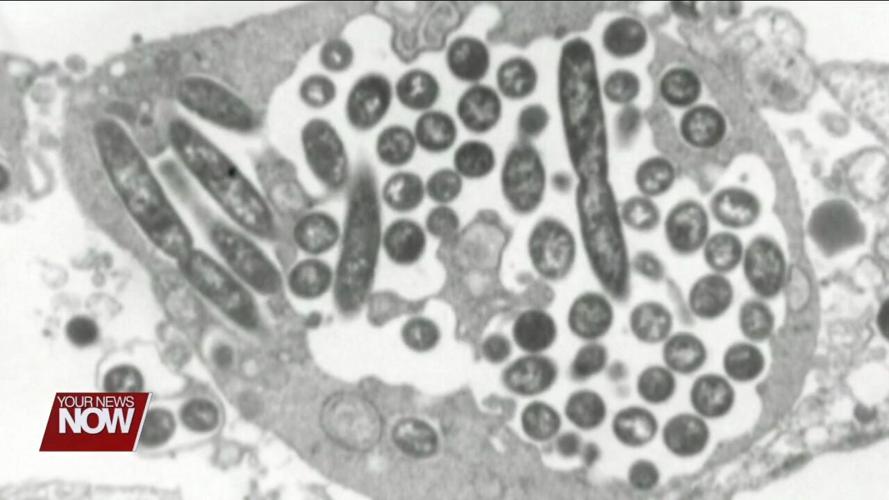

According to the Centers for Disease Control and Prevention, Legionnaires' disease is a severe form of pneumonia caused by the Legionella bacteria. Symptoms may include fever, cough, headaches, shortness of breath, and muscle aches.